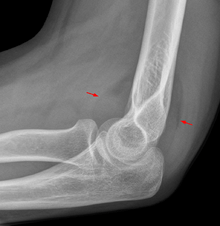

Fat pad sign

On an elbow X-ray, the fat pad sign, also known as the sail sign, suggests an occult fracture. Its name derives from the fact that it has the shape of a spinnaker (sail).[1] It is caused by displacement of the fat pad around the elbow joint. Both anterior and posterior fat pad signs exist, and both can be found on the same X-ray.

In children, a posterior fat pad sign suggests a condylar fracture of the humerus. In adults it suggests a radial head fracture. The fat pad sign only occurs after an intra-articular fracture.

The fat pad sign is invaluable in assessing for the presence of an intra-articular fracture of the elbow. An anterior fat pad is often normal. However a posterior fat pad seen on a lateral x-ray of the elbow is always abnormal. The patient will be unable to flex their elbow and requires orthopaedic input.[2]